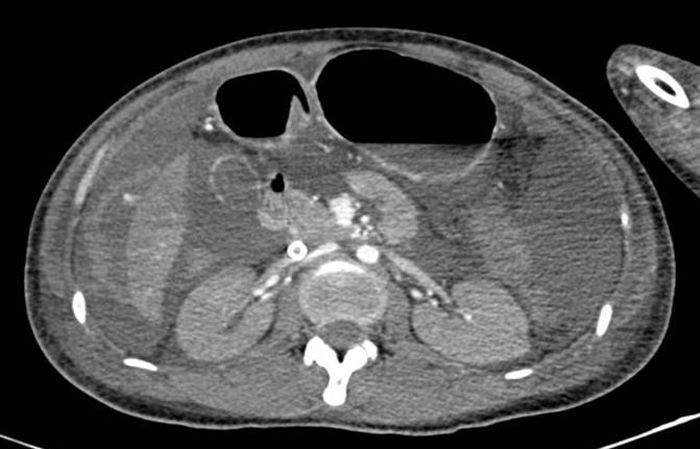

Dịch ổ bụng lượng nhiều, nghi ngờ chảy máu ổ bụng trên phim chụp cắt lớp vi tính. Ảnh: BVCC

Ngay lập tức, bệnh viện đã huy động khẩn cấp nguồn máu từ Bệnh viện Truyền máu Huyết học và kêu gọi hiến máu từ toàn thể nhân viên. Qua siêu âm và chụp cắt lớp, ê-kíp phát hiện ổ chảy máu vùng gan.